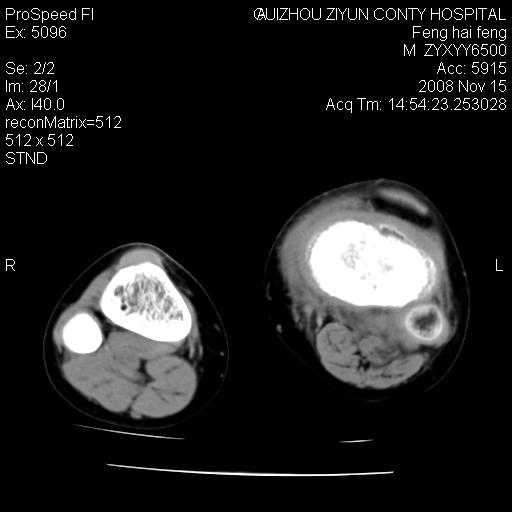

标题: CT16656:M 14Y 左膝关节肿胀一年余。其余病史不详。 [打印本页]

标题: CT16656:M 14Y 左膝关节肿胀一年余。其余病史不详。

考虑左侧髌骨结核;左膝关节滑膜肿胀、增厚,关节囊积液。

左膝滑膜型关节结核可能性大!支持!滑膜型关节结核主要ct表现:关节囊肿胀,积液,关节面见小破坏灶,并见点状死骨!

好大的左腿!考虑左侧髌骨结核,左膝关节滑膜肿胀、增厚,关节囊积液。

左侧髌骨结核;左膝关节滑膜肿胀、增厚,关节囊积液